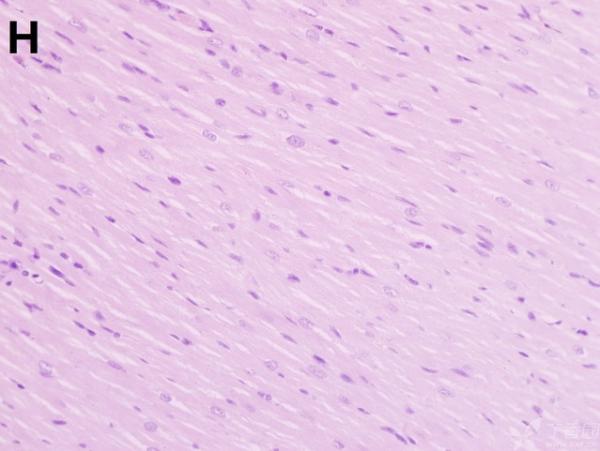

ÎÒ½«Ã¿¸ö×éÖ¯ÅÄÁË3¸öÊÓÒ°£¬ÒÔ±ã×ۺϷÖÎö£¬Âé·³¸÷λ°ïÎÒ°ÑA¡¢B¡¢C¡¢D¡¢E¡¢F¡¢GµÄËðÉË´óСÅŸö˳Ðò ÔÙ°ÑA¡¢B¡¢C¡¢H¡¢I¡¢JËðÉ˵ÄÑÏÖØ³Ì¶ÈÅŸöÐò¡£¸ÃÎÊÌâÒ²ÔÚ¶¡ÏãÔ°ÉÏÇóÖúÁË£¬Á´½Óhttp://www.dxy.cn/bbs/topic/23986562 A1.jpg A2.jpg A3.jpg B1.jpg B2.jpg B3.jpg C1.jpg C2.jpg C3.jpg D1.jpg D2.jpg D3.jpg E.jpg F1.jpg F2.jpg F3.jpg G1.jpg G2.jpg G3.jpg H1.jpg H2.jpg I.jpg I2.jpg I3.jpg J.jpg J2.jpg J3.jpg [ Last edited by ÀëÈËÏæÑÅÀá on 2012-10-9 at 21:11 ] |